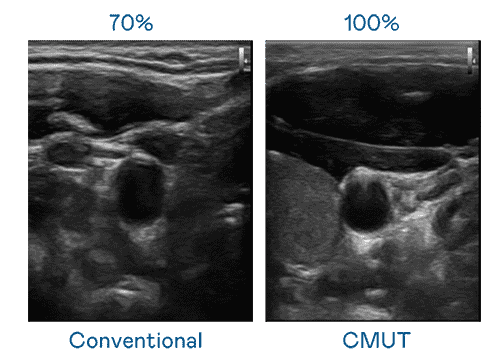

CMUT 技术是一种用电容式微机电元件来产生超音波讯号的技术。。。与传统 PZT 压电式技术相比,,,CMUT 频宽增加 30%,,,,更宽频的超音波讯号让影像解析度大幅提升,,,是实现高影像品质医疗超音波扫描、、、、促进精准医疗发展的关键技术。。

大频宽带来超清晰影像

超音波影像的解析度高低,,,首先取决于探头能发出的讯号频宽。。。彩运网 CMUT 可提供高清晰的超音波讯号,,,提供高频宽、、、、高灵敏度、、影像纹理细节更高的超音波影像,,协助医护人员缩短影像判读时间及利用精准的医疗影像进行诊断。。